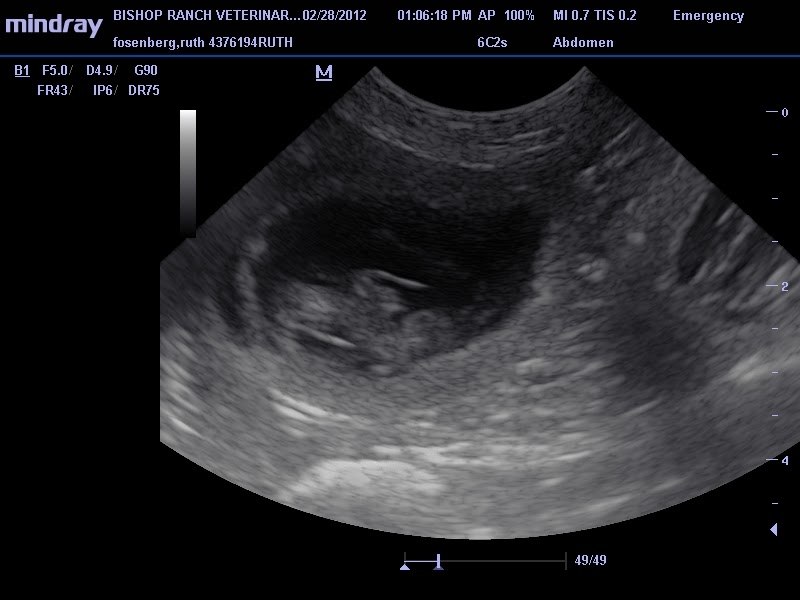

The only difference for an animal is that the fur needs to be clipped away a bit. Dog in dorsal recumbency, with the ultrasound transducer positioned in a transverse imaging plane at the level of the 11th intercostal space and the notch pointing dorsally (a); Bowel obstruction in dogs can be caused by ingesting objects and may be dangerous if left untreated. Dog ultrasound scan approx 35 days post mating.